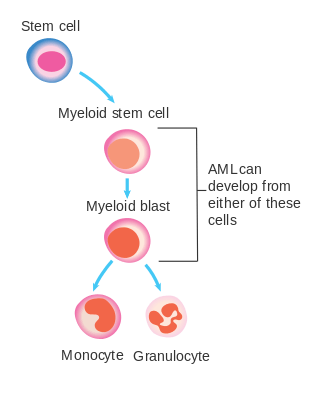

The malignant cell in AML is the myeloblast. In normal hematopoiesis, the myeloblast is an immature precursor of myeloid white blood cells; a normal myeloblast will gradually mature into a mature white blood cell. In AML, though, a single myeloblast accumulates genetic changes which "freeze" the cell in its immature state and prevent differentiation.[30] Such a mutation alone does not cause leukemia; however, when such a "differentiation arrest" is combined with other mutations which disrupt genes controlling proliferation, the result is the uncontrolled growth of an immature clone of cells, leading to the clinical entity of AML.[31]

Much of the diversity and heterogeneity of AML is because leukemic transformation can occur at a number of different steps along the differentiation pathway.[32] Modern classification schemes for AML recognize the characteristics and behavior of the leukemic cell (and the leukemia) may depend on the stage at which differentiation was halted.